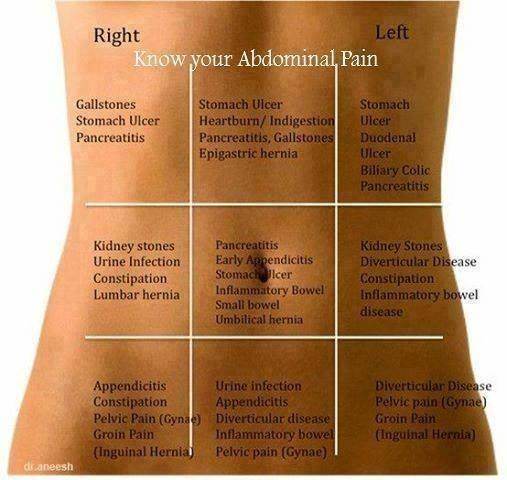

Pin on Abdominal Pain

Pin on Symptoms and Conditions

Causes of Pain in the Right Side | New Health Advisor

right lower abdomen body organs

What Can Cause Right Side Abdominal Pain?

Pin on All about Health

Abdominal and Pelvic Pain in the Nonpregnant Female | Tintinalli’s …

Lower Abdominal Pain: Symptoms And Causes – Forbes Health

Abdominal pain | Health | Pinterest | Pain d’epices and Abdominal pain

Human Body Right Side – ovulation symptoms

What Is Pain In Lower Right Side Of Stomach – StomachGuide.net

Lower Back Internal Organs – What Organs Are On The Right Side Of Your …